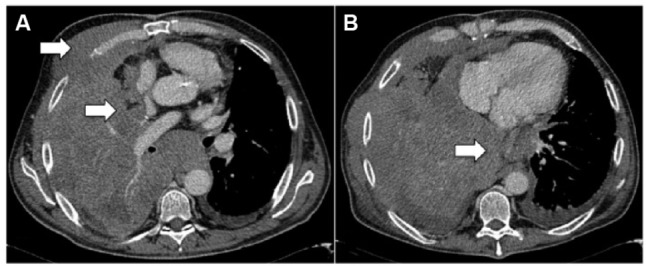

恶性胸膜间皮瘤(MPM)是一种治疗选择有限的疾病,其管理仍然存在争议。通常通过胸腔镜进行诊断,允许多次活检并进行组织学分型,并用于外科候选人的分期目的。国际间皮瘤兴趣小组和国际肺癌研究协会建立的TNM分期系统是临床使用的推荐和最近更新的分类,该系统主要基于手术和病理变量以及横断面成像。对比增强计算机断层扫描是主要的成像程序。目前,最常用的MPM测量系统是改进的实体肿瘤反应评价标准(RECIST)方法,该方法基于垂直于胸壁或纵隔的肿瘤厚度的一维测量。磁共振成像和18f -氟-2-脱氧-d -葡萄糖正电子发射断层扫描的功能成像可以提供额外的分期信息在选择的情况下,尽管这种方法的有用性是有限的患者接受胸膜切除术。MPM的分子重分类和基因表达或miRNA预后模型有可能改善预后和患者选择适当的治疗算法;然而,他们等待在临床实践中引入前瞻性验证。

Malignant pleural mesothelioma (MPM) is a disease with limited therapeutic options, the management of which is still controversial. Diagnosis is usually made by thoracoscopy, which allows multiple biopsies with histological subtyping and is indicated for staging purposes in surgical candidates. The recommended and recently updated classification for clinical use is the TNM staging system established by the International Mesothelioma Interest Group and the International Association for the Study of Lung Cancer, which is based mainly on surgical and pathological variables, as well as on cross-sectional imaging. Contrast-enhanced computed tomography is the primary imaging procedure. Currently, the most used measurement system for MPM is the modified Response Evaluation Criteria in Solid Tumors (RECIST) method, which is based on unidimensional measurements of tumor thickness perpendicular to the chest wall or mediastinum. Magnetic resonance imaging and functional imaging with 18F-fluoro-2-deoxy-D-glucose positron-emission tomography can provide additional staging information in selected cases, although the usefulness of this method is limited in patients undergoing pleurodesis. Molecular reclassification of MPM and gene expression or miRNA prognostic models have the potential to improve prognostication and patient selection for a proper treatment algorithm; however, they await prospective validation to be introduced in clinical practice.